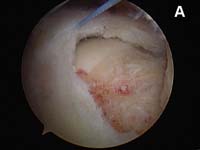

The video below is a diagnostic arthroscopy procedure as viewed from the back of the joint looking to the front. This patient has mild, partial thickness fraying at the rotator cuff insertion. This tear is analogous to the tear show in Fig. 5.

- partial-thickness or incomplete tears can occur. While these tears may progress to complete tears, rehabilitation can frequently strengthen the remaining intact cuff tissue and halt the process. Many persons with partial-thickness tears will never require surgery if they undergo an appropriate physical therapy rehabilitation to address muscle imbalances. (See Fig. 5. and video above)